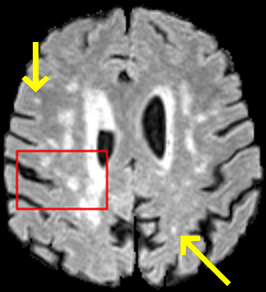

To test the impact of the iterative refinement on YODA’s translation quality, we compared regression and diffusion sampling on the RS data and present additional generation examples in Fig. 6. We observe that diffusion sampling visually resembles the appearance of the acquired images. Regression sampling preserves key anatomical features – the GM/WM boundary, WMHs (Fig. 4), the outline of the pallidum (Fig. 6) – but omits many high-frequency features. To investigate whether iterative refinement during diffusion sampling adds relevant and systematic medical information or only imitates acquisition noise, we performed ExpA sampling, i.e. averaging the output of several ( or ) diffusion trajectories. We observed a gradual loss of high-frequency details when increasing the (see also the supplementary video), indicating that the effect of the iterative refinement is non-systematic. For , the images are visually almost indistinguishable from the initial regression solution (see the supplementary video, and Fig.4 and 6). We directly compared the synthesis results of ExpA () and regression sampling quantitatively and found the differences to be minimal (SSIM: 99.73%, PSNR: 45.30 dB), i.e. diffusion sampling approaches the initial regression solution for a high . The quantitative analysis of the image quality (Tab. 1) showed that diffusion sampling impairs the assessed SSIM and PSNR in comparison to regression sampling for both the in- and external test sets, which we attribute to noise generation (Sec. 3.1). In turn, ExpA averages improved both metrics and, for , performed mostly on par with the regression solution in both test sets in terms of SSIM, while the PSNR in the RS was slightly increased (Tab. 1). However, we observed that ExpA sampling YODA improves the replication of systematic 3D low-frequency image intensity drifts (bias fields) due to the 3D synchronization in 2.5D diffusion sampling. Yet, this apparent advantage did not generalize to the external MBB dataset, as bias fields are MR protocol-specific.

On the RS data (Tab. 1), regression sampling of YODA significantly outperformed all competing methods both w.r.t. the image quality and – except the ALVR for MADM – downstream WMH segmentation, whereas the DB of Choo et al. [31] achieved an higher WMH CNR.

When analyzing the RS synthesis results (Fig. 4), we noted that most reference methods strive to imitate realistic images, but several artifacts can be observed such as hallucinated WMHs (SynDiff) and salt-and-pepper noise (SynDiff, I2I-Mamba, ResViT).